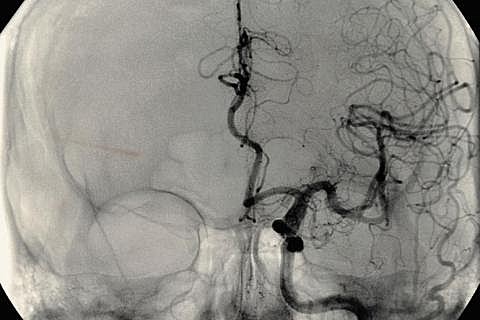

• Angiografía

Angiografía

Antonio E. Moniz considerado el inventor de la lobotomía, siendo así el preponderante en el desarrollo de la angiografía cerebral.